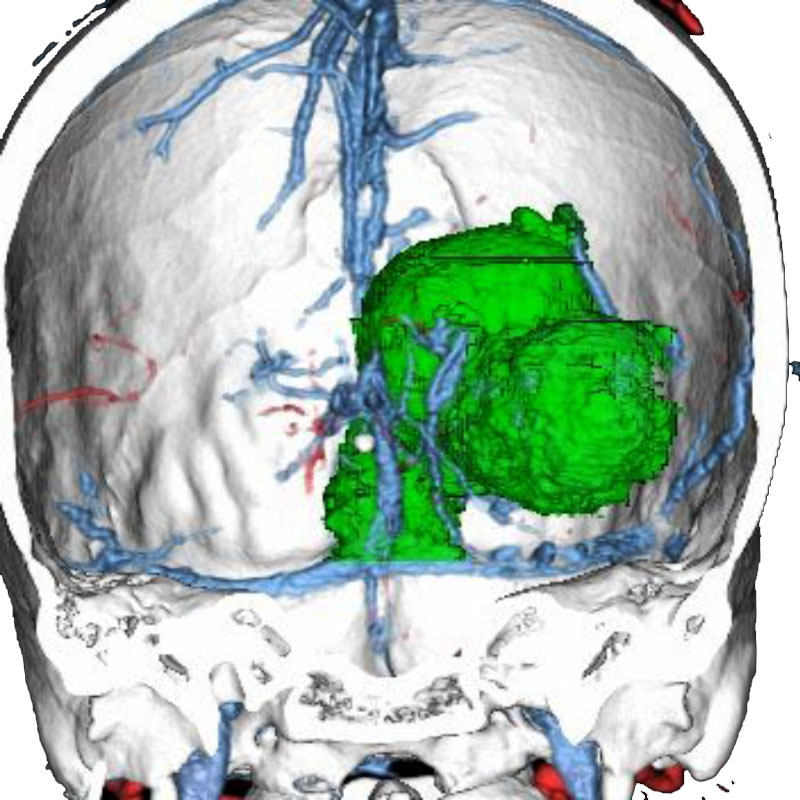

脳動静脈奇形

血管塞栓術

松田/濵田/元永